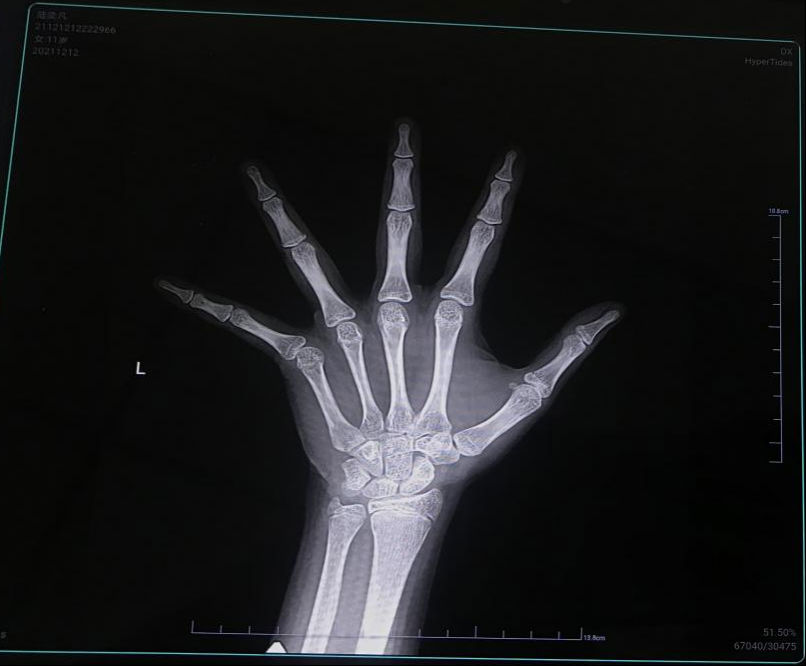

判断孩子还能不能长、能长多少,要看孩子的骨龄状况。通过拍摄孩子左手腕部分的X光片,能看到孩子生长空间、潜力有多少。 孩子骨骺一旦闭合,孩子就很难增高了!